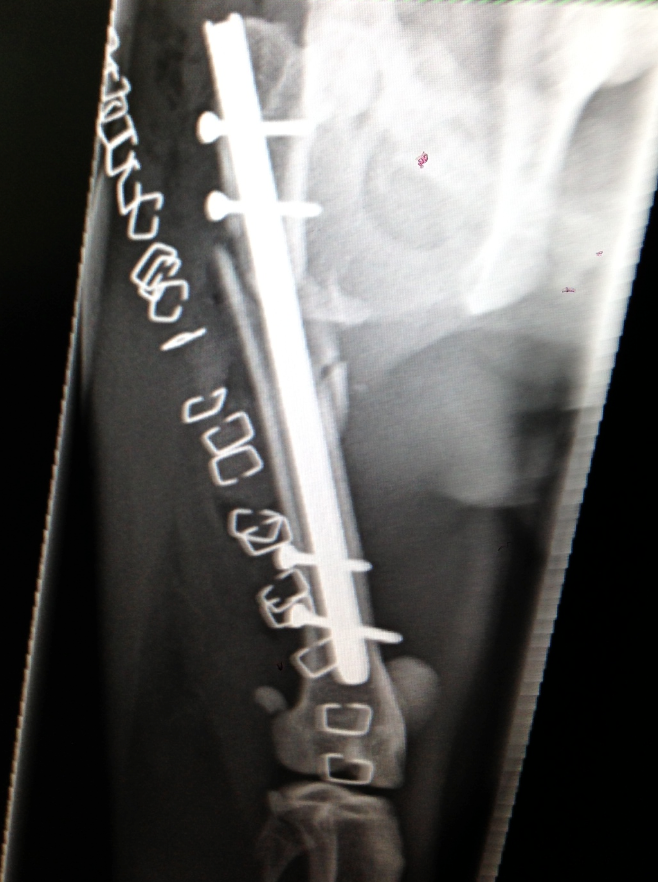

Dr Sam Haynes used an Interlocking nail repair

Dr Sam Haynes managed to repair the break with an interlocking nail, and has produced some great post operative results.

Geoffrey has a good prognosis and should be fully healed up in about 3 months time. He is expected to walk normally without a limp by the time healing is complete. The bone fragments will heal together and ossify, then re-model to normal bone over time.

Interlocking nail repair techniques are often used in severe breaks of this nature.